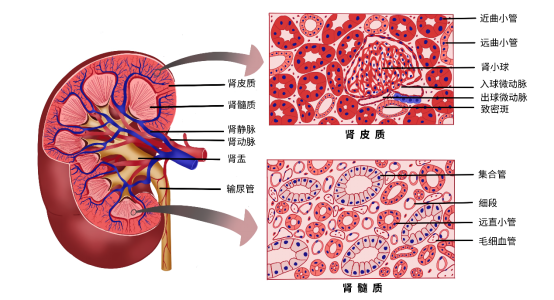

一等奖作品(2):新冠肺炎病理形态 作者:18级临床医学 李臻